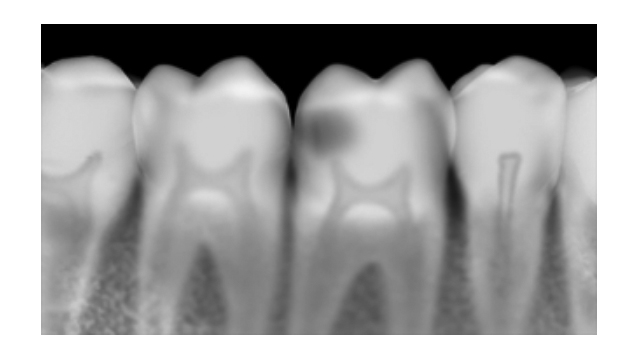

Perfect diagnostic image quality

The Agfa Dentus range comprises intra-oral and extra-oral X-ray films. It is supported by suitable intensifying screens, film cassettes for extra-oral exposures and processing chemicals. The X-ray films for intra-oral and extra-oral applications are available in all the standard formats used in practices. All the Agfa Dentus X-ray films provide high image quality at a low radiation dose.